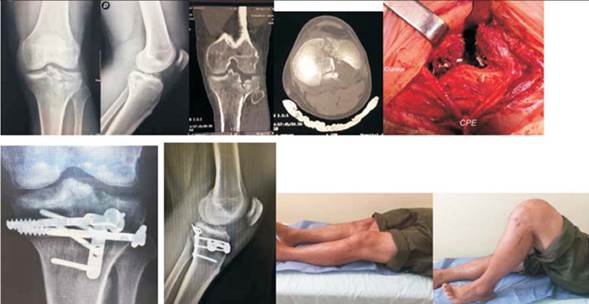

1. Paciente de 37 años. Sexo masculino. Accidente de moto. Fractura grado IV de Schatzker. Ensanchamiento de la metáfisis sin luxación. Se observa un gran fragmento PM sin hundimiento y compromiso PL con hundimiento mayor de 5 mm. Se realiza abordaje PM y se fija el fragmento con placa DCP 4.5. Con asistencia artroscópica y por una pequeña ventana anterolateral se levanta la depresión PL. Corresponde al caso Nº14 de la tabla 3 (figura 8).